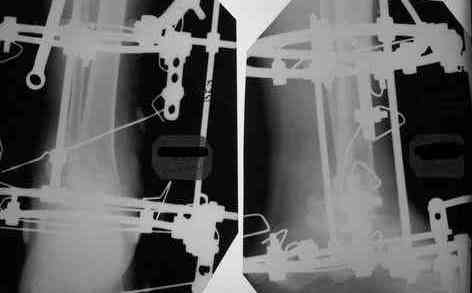

Уважаемые коллеги. Тема обсуждалась: Прошу прощения за задержку с ответом. Женщину прооперировал. Из внутреннего доступа удалена внутренняя лодыжка, из наружного отсечена от рубцов латеральная, из обоих параллельно предыдущей остеотомии экономно произведена резекция "суставных" поверхностей ББК и тарана до "кровавой росы", удалены все рубцы, стопа выведена, провизорная диафиксация спицами. Далее аппарат, однако, после удаления диафиксирующих спиц и компрессии, произошло наружное смещение тарана. Но и так время операции составило почти 4 часа, поэтому через неделю пришлось маленько подработать аппаратом. Итог на снимках (извиняю сь за качество). Не совсем все нравится - в литературе намного красивее. Только один вопрос к уважаемому форуму: что действительно необходимо подправить? Спасибо. С уважением, А.Минервин.

Стопа сильно смещена кзади, если не ошибаюсь из-за маленького размера снимка.

Смещение стопы кзади видно более отчетливо. Это намеренно так сделано, поскольку так сформировались контактные поверхности?

В Campbell`s рекомендуется смещение тарана чуть кзади (чуть- цифры нет), но контакт действительно в таком положении получился максимальным, хотя, я думаю, тоже можно постепенно переместить, если это критично.

You want to have your heel as posterior, especially when the contact is better, but also for good lever (Ri4ag) for the gastroc complex.AL

Здравствуйте, Алексей Юрьевич. Угол голень-стопа 98 градусов. Но пока не поздно его уменьшить (до 90?). Сейчас больная ходит с каблуком 3 см.

Небольшей эквинус при артродезе нужен. В данном случае угол между пяткой и большеберцовой примемлемый, а передний отдел стопы за счет суставов среднего тарза остается подвижен.

Рассмотрел демонстрируемые картинки. Аппарат наложен без любви к методу.

Погрешности мелкие, на исход лечения вряд ли повлияют. Но все же. По-моему не одинаковые кольца, не корректно введенный согнутый стержень Шанца, проксимальные чрескостные элементы расположены на одной опоре (база на голени вполне могла бы быть из двух колец) и совсем мелкие замечания - грубо загнутые не скушенные концы спиц, местами не отмытая скорее всего с момента операции с конечности и аппарата кровь.

Выполнить задуманную работу можно и аппаратом наложенным с погрешностями, но я говорю о эстетической стороне вопроса. Блестящий, без капельки крови, "весь в осях" аппарат "влитый" в ногу и смотрящейся как крепкий гриб-боровичок ошеломляет пациента и родственников и вселяет в них обоснованную надежду, что теперь то все будет хорошо. Синтез металла и живого тела своей красотой впечатляет и врачей других специальностей. Об этом я и пишу. Последнее время я практически не вижу и правильно, элегантно наложенных гипсовых повязок.